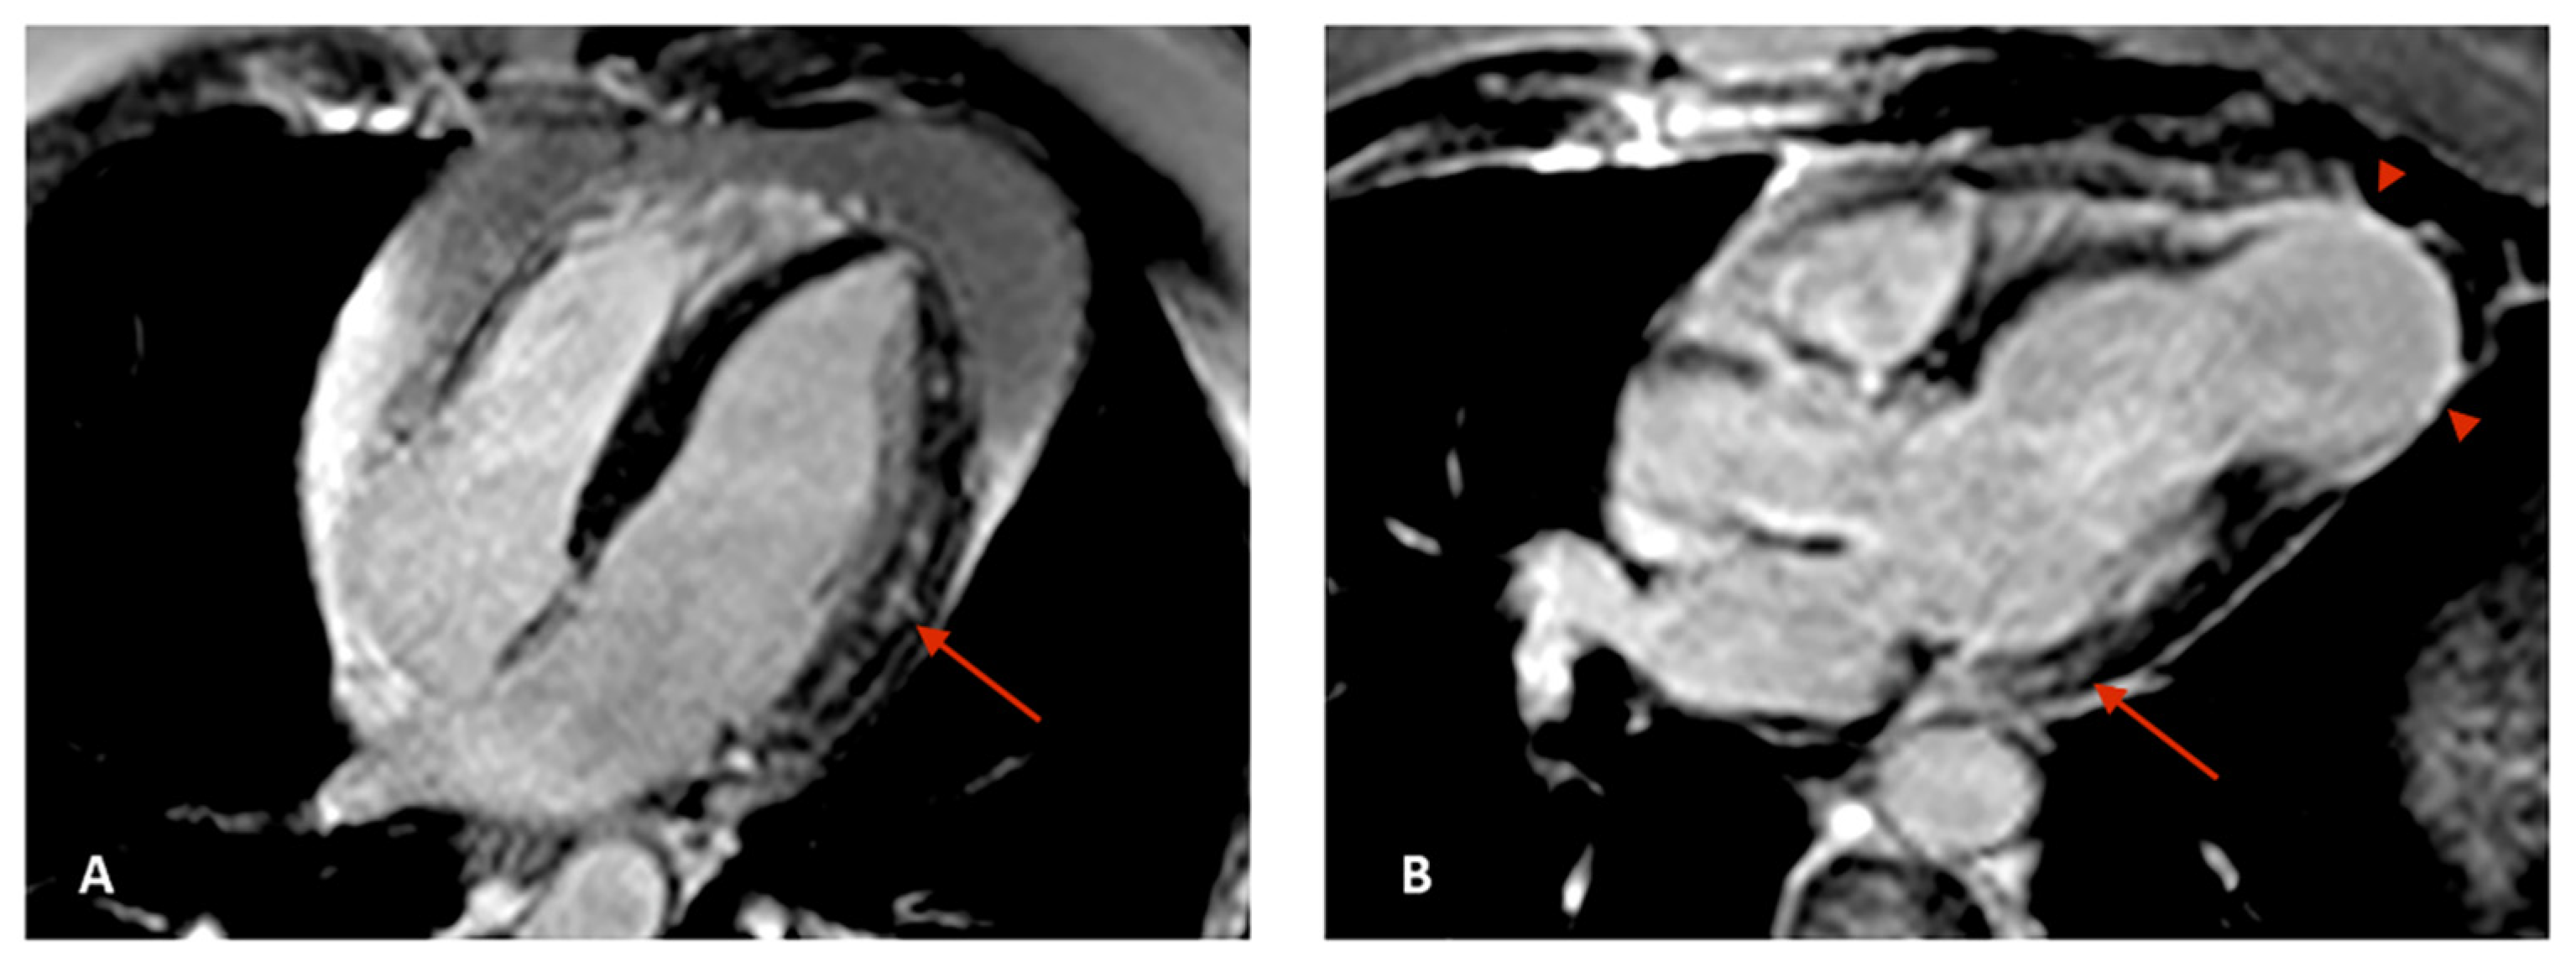

- Senra, T.; Ianni, B.M.; Costa, A.C.; Mady, C.; Martinelli-Filho, M.; Kalil-Filho, R.; Rochitte, C.E. Long-term prognostic value of myocardial fibrosis in patients with chagas cardiomyopathy. J. Am. Coll. Cardiol. 2018, 72, 2577–2587. [Google Scholar] [CrossRef]

- Regueiro, A.; García-Álvarez, A.; Sitges, M.; Ortiz-Pérez, J.T.; De Caralt, M.T.; Pinazo, M.J.; Posada, E.; Heras, M.; Gascón, J.; Sanz, G. Myocardial involvement in Chagas disease: Insights from cardiac magnetic resonance. Int. J. Cardiol. 2013, 165, 107–112. [Google Scholar] [CrossRef]

- Mello, R.P.D.; Szarf, G.; Schvartzman, P.R.; Nakano, E.M.; Espinosa, M.M.; Szejnfeld, D.; Fernandes, V.; Lima, J.A.; Cirenza, C.; De Paola, A.A. Delayed enhancement cardiac magnetic resonance imaging can identify the risk for ventricular tachycardia in chronic Chagas’ heart disease. Arq. Bras. Cardiol. 2012, 98, 421–430. [Google Scholar] [CrossRef]

- Volpe, G.J.; Moreira, H.T.; Trad, H.S.; Wu, K.C.; Braggion-Santos, M.F.; Santos, M.K.; Maciel, B.C.; Pazin-Filho, A.; Marin-Neto, J.A.; Lima, J.A. Left ventricular scar and prognosis in chronic chagas cardiomyopathy. J. Am. Coll. Cardiol. 2018, 72, 2567–2576. [Google Scholar] [CrossRef]

- Torreão, J.A.; Ianni, B.M.; Mady, C.; Naia, E.; Rassi, C.H.; Nomura, C.; Parga, J.R.; Avila, L.F.; Ramires, J.A.; Kalil-Filho, R. Myocardial tissue characterization in Chagas’ heart disease by cardiovascular magnetic resonance. J. Cardiovasc. Magn. Reson. 2015, 17, 97. [Google Scholar] [CrossRef]